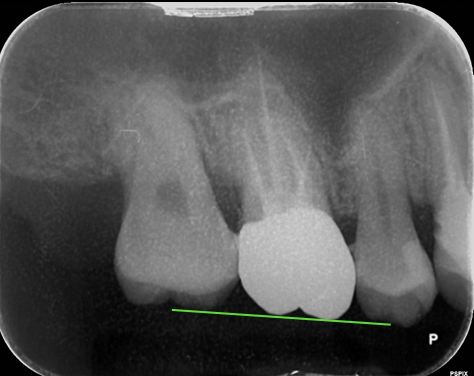

「矯正的歯の圧下」って何?

治療前

治療後

- 歯を失ってそのままにしていたり、銀歯が外れたまま放置していると噛み合う上の歯が伸びてきて、インプラントやセラミックを入れるスペースがない

- 咬合平面が乱れていて、干渉を起こしている

このような場合、いきなり補綴やインプラントをしてしまうと、見た目・噛み合わせ・清掃性に問題が残ります。

そこで矯正的に歯を少しずつ沈めることで、理想的な歯肉ラインや骨の高さ、補綴スペースを整えるのです。